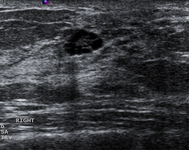

Avaliação de massa mamária

Imagem ultrassonográfica de um carcinoma complexo

Cortesia do Dr. Lane Roland, Universidade de Louisville; usado com permissão